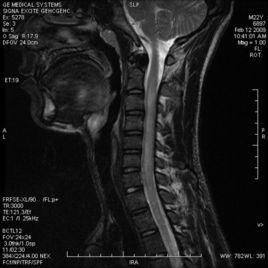

2)MRI:脊髓腫脹,長T1T2信號